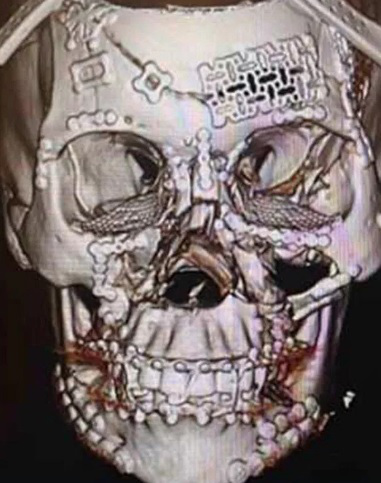

Η φωτογραφία που βλέπετε απεικονίζει το «πριν» και το «μετά» της εκτενούς αναδόμησης κρανίου στην οποία υποβλήθηκε μια γυναίκα, που φέρεται να ενεπλάκη σε τροχαίο ατύχημα.

Όπως βλέπετε, δεν είναι μόνο η άνω και κάτω γνάθος που έχει διαλυθεί, αλλά το κρανίο έχει σπάσει και θρυμματιστεί σε διάφορα σημεία, με τα κομμάτια του απλώς να… επιπλέουν. Έχουν τοποθετηθεί σχεδόν παντού λάμες.

Σύμφωνα με επίσης ανεπιβεβαίωτες πληροφορίες, η χειρουργική επέμβαση για την αναδόμηση του κρανίου και του προσώπου της γυναίκας διήρκεσε οκτώ ώρες όπως αναφέρει η iatropedia.gr

Ένας οφθαλμίατρος δημοσίευσε τις εικόνες που βλέπετε σε έναν ιατρικό ιστοχώρο, όπου έχουν πρόσβαση χειρουργοί, για να αναρτούν υποθέσεις ασθενών και να ξεκινούν σοβαρές συζητήσεις με συναδέλφους τους σχετικά με κάποια διάγνωση ή ενδεχόμενη χειρουργική επέμβαση.

Το ατύχημα φέρεται να συνέβη πριν από δύο χρόνια, αλλά οι εικόνες έχουν επανεμφανιστεί σε ιστότοπους κοινωνικής δικτύωσης, με πολλούς να επαινούν τη χειρουργική ομάδα πίσω από την απίστευτη αναδόμηση κρανίου. Σύμφωνα με τον οφθαλμίατρο που δημοσίευσε τις εικόνες, η ασθενής έχει αναρρώσει πλήρως.

Ο χειρουργός έγραψε κάτω από την εικόνα #1 που βλέπετε: «Αυτή η σάρωση δείχνει την ολοκληρωμένη αναδόμηση του προσώπου. Χάρη σε μια ειδική πολυεπιστημονική ομάδα, η ασθενής αναρρώνει καλά».

Κοιτάξτε προσεκτικά την εικόνα «μετά» και θα είστε σε θέση να παρατηρήσετε όλα τα μικρά κομμάτια που οι χειρουργοί επανατοποθέτησαν στο κρανίο της ασθενούς για να αποκτήσει και πάλι πρόσωπο αλλά και λειτουργική χρήση του σαγονιού της

Εικόνα 2: Το «μετά»